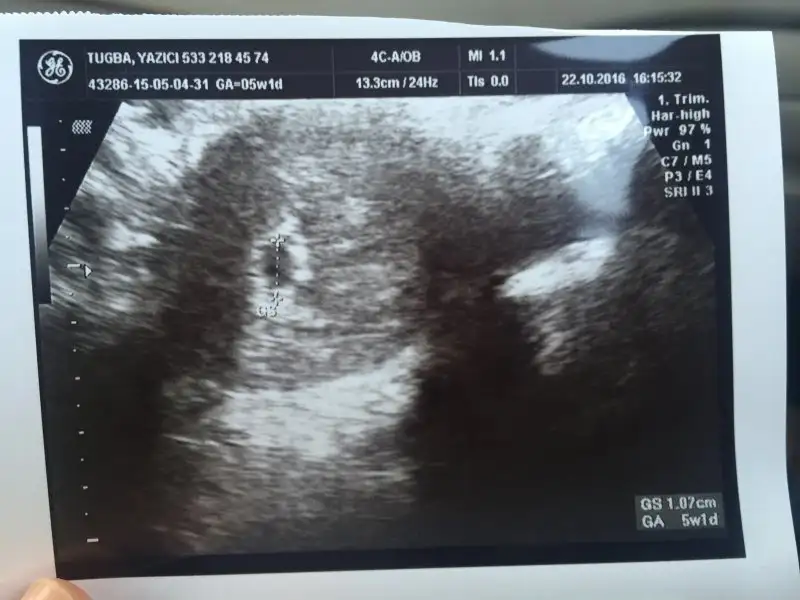

Bugün kontrolüm vardı, çok sükür keseyi gördük :anneadayı: 2 hafta sonra kalp atışını duyarız dedi. Benim de hesapladığım gibi 5+1 mişiz çok şükür :KK46:işte bu da bizim kesemiz :nazar::KK200:

Eklentiler

• image.webp

image.webp

25,7 KB · Görüntüleme: 60